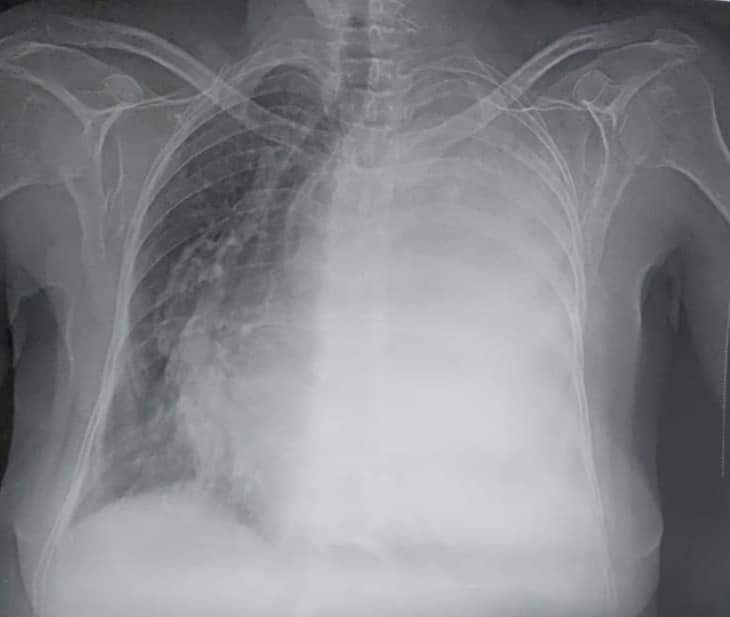

قال الدكتور محمد احمد الجزار إستشاري جراحة القلب والصدر في تصريحات صحفية اليوم بمستشفي بنها الجامعي ان الحالة كانت لمريضة تبلغ من العمر ٦٠ سنة كانت تعاني من ضيق بالتنفس ونهجان لأقل مجهود وبعد الفحوصات والاشعات تم اكتشاف وجود انسكاب بللوري شديد علي الرئة اليسري أدي إلي انضغاط الرئة اليسري ودفع القلب والقصبة الهوائية للجهة الأخري (اليمني).